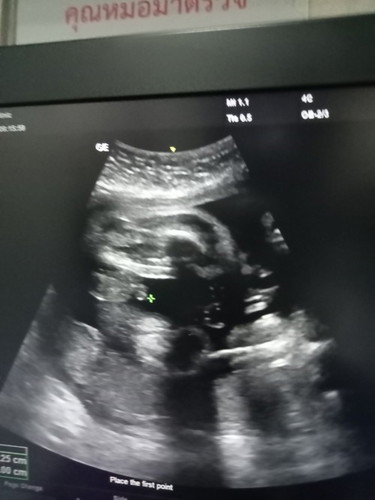

31weekรู้เพศสักที

31weekกว่าจะรู้เพศลุ้นแทบตายอยากได้ลูกชายสมดั่งใจเลยค่ะ